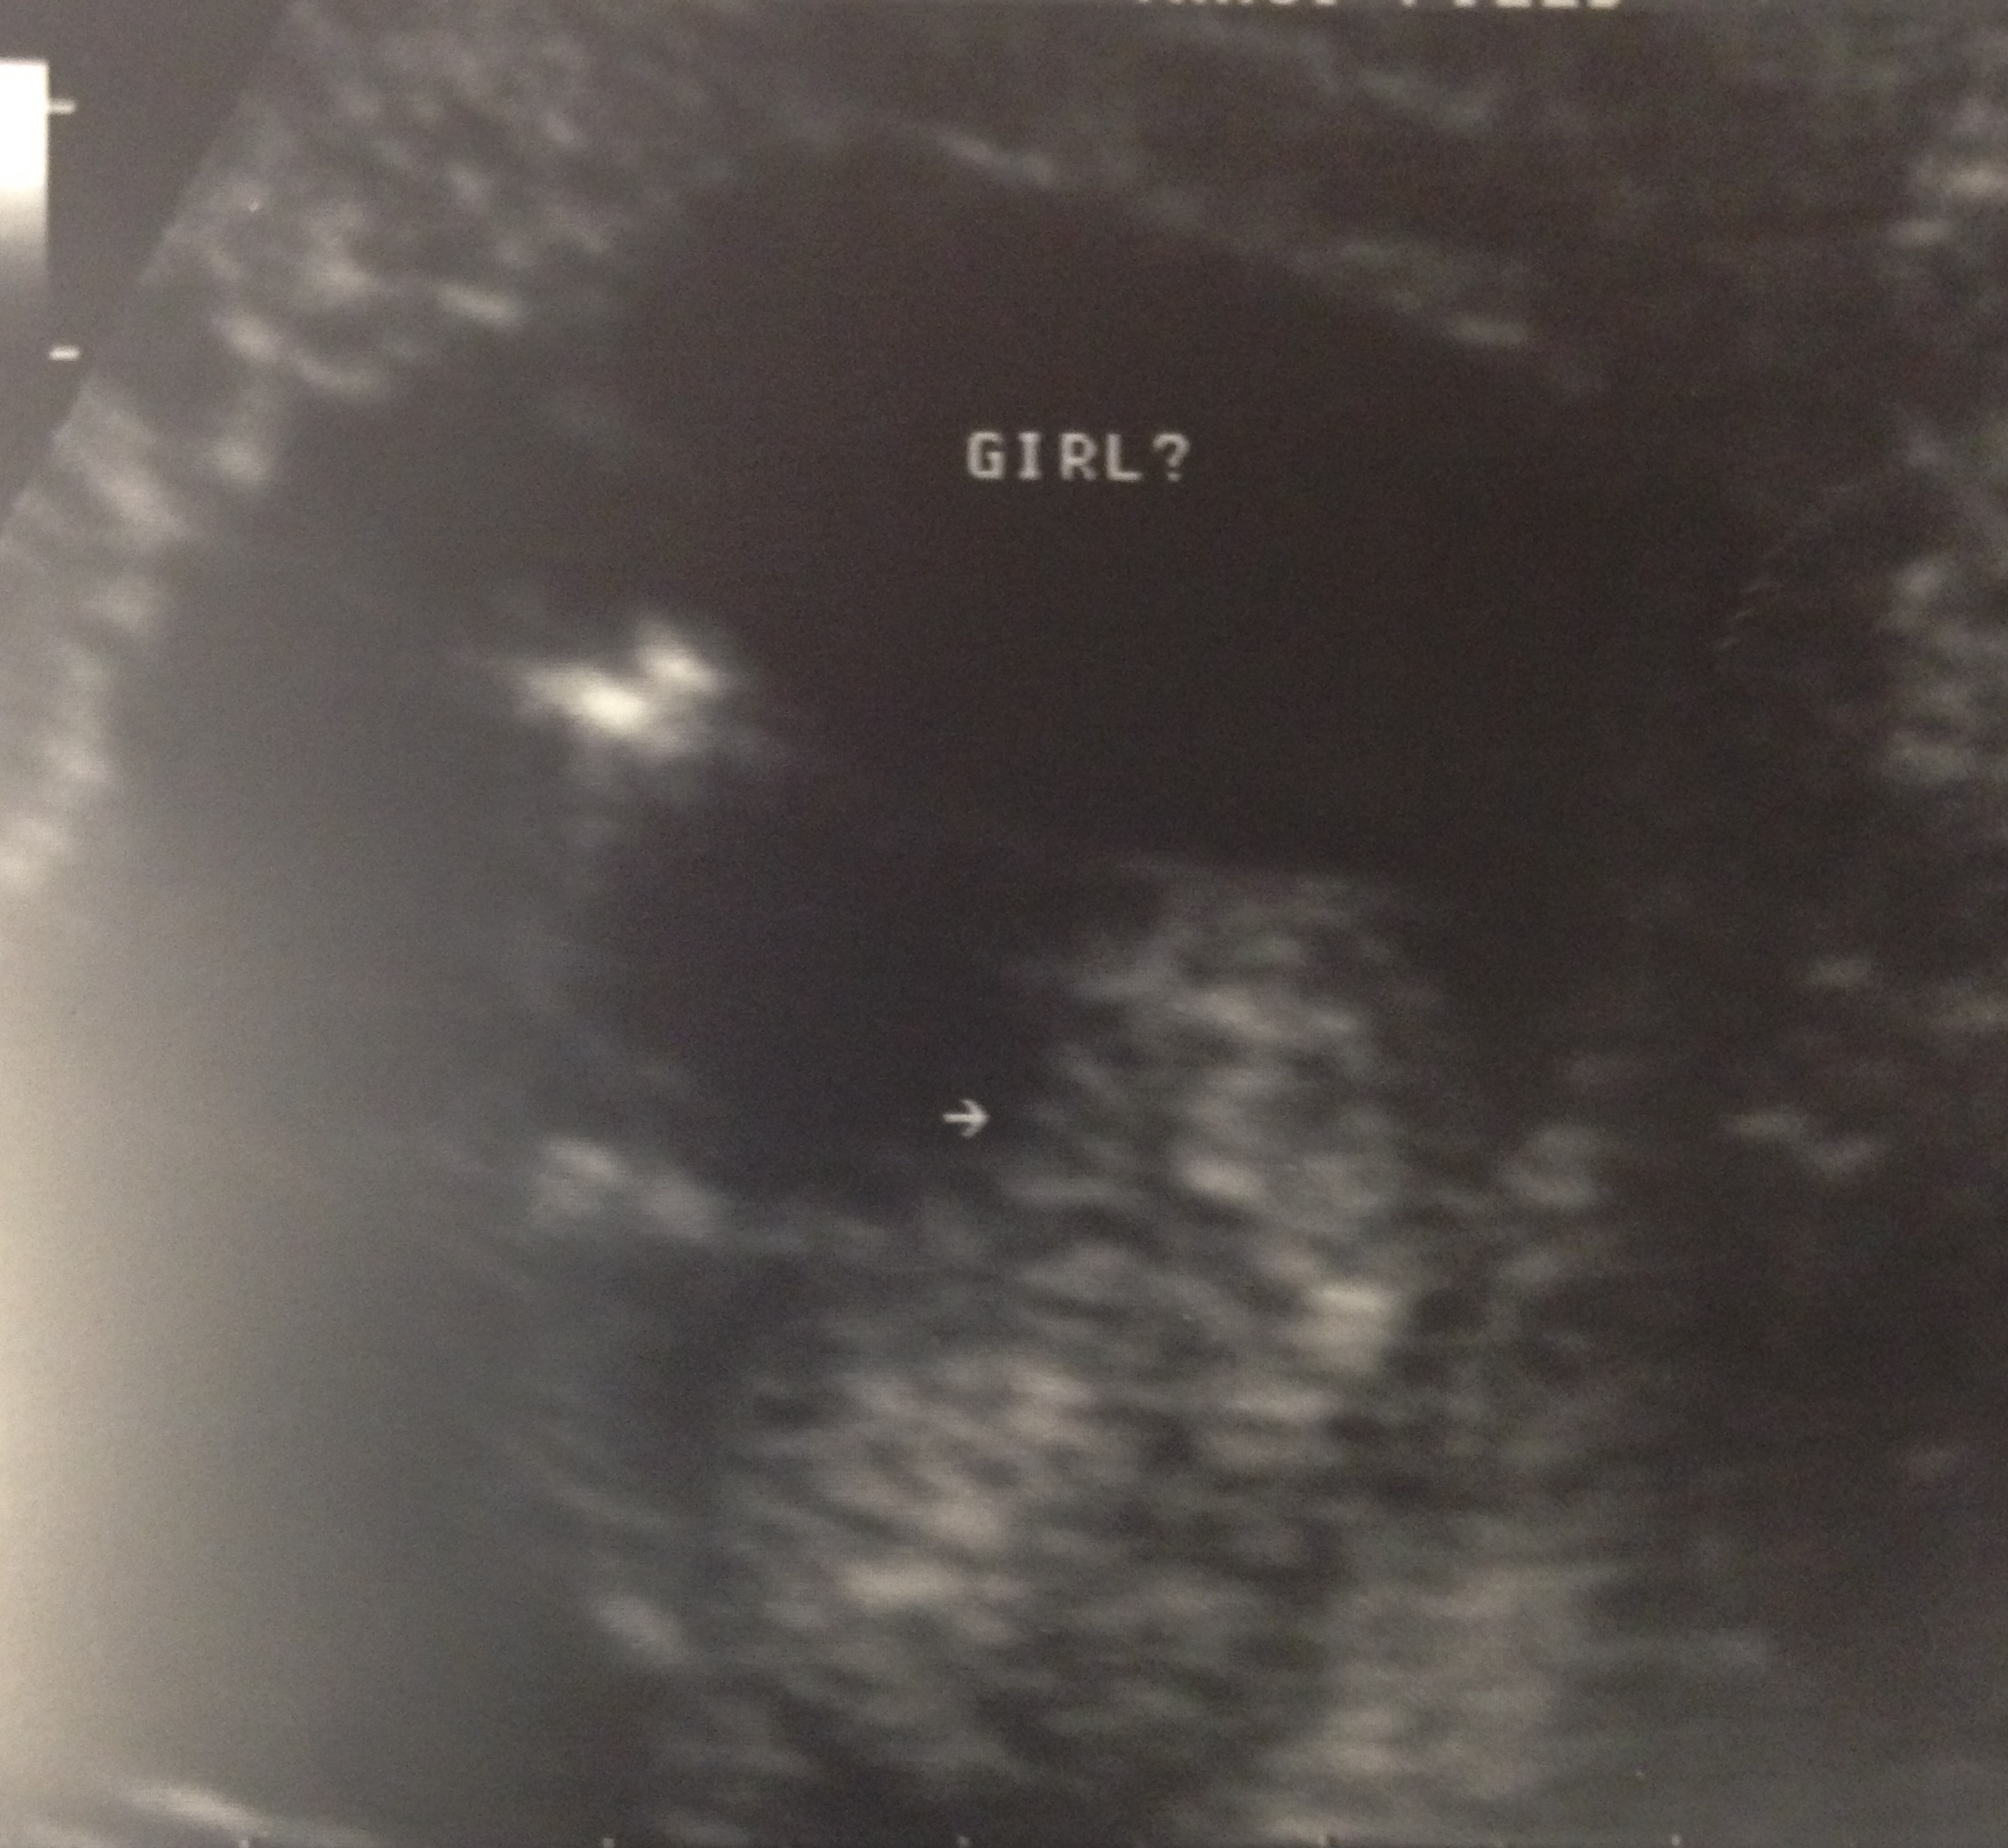

Had another ultrasound yesterday at 14 weeks 1 day. Tech still thinks girl. Wanted to post here for your feedback!

Sorry if this is a stupid question, but I'm terrible at deciphering ultrasound pics! In the second pic, the tech drew an arrow to three faint lines that appear to be fanning out. Behind those (to the right in the pic) are another set of three lines. Can you tell me which set you're looking at? Could the first (fanned out) set be the umbilical cord? I heard that the cord can sometimes show as three lines too.